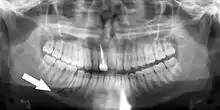

![]() | |

| A broken upper front tooth. The layers of tissue that make up the tooth are clearly visible, with the pink pulp standing out against the paler dentine and tooth enamel. | |